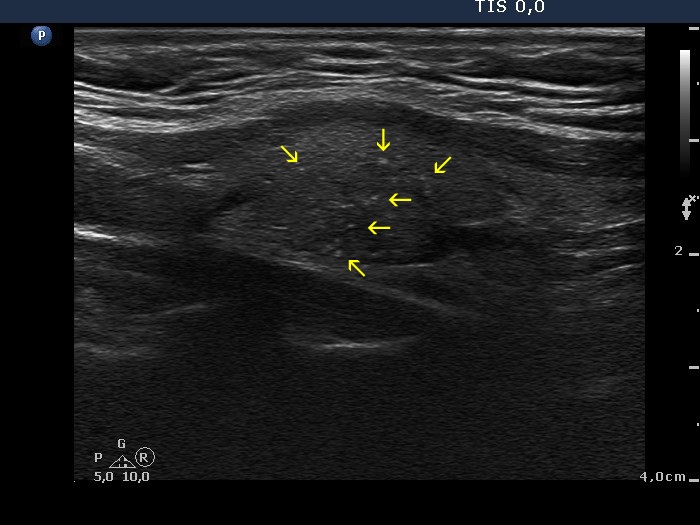

Papillary carcinoma (histology) - case conp014

Transverse scan

Longitudinal scan

This is not a decisive but only a suspicious pattern. Lower to the main body of the tumor, there are several microcalcifications (yellow arrows). The presence of these isolated microcalcifications raises the possibility of infiltrative spread of the tumor. Although the less hypoechogenic area pointed with red arrows dorsal to the tumor might be also presentation of extrathyroidal spread, such pattern has limited if any relevance; a focus of thyroiditis might be also the cause. Be aware that the main difference between the non-specific finding in the left image and the suspicious pattern in the right image is based on the lack (left) and the presence (right) of microcalcifications. The possibility of extrathyroidal spread should be also considered: the ventral part of the nodule cannot be distinguished from the strap muscle running on the ventral surface of the lobe.